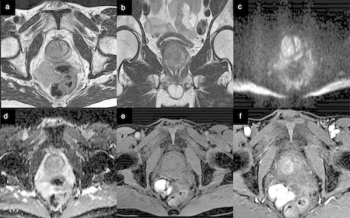

For patients who had previous radiotherapy for prostate cancer (PCa), researchers found that a biparametric MRI-based deep learning model demonstrated an 81.5 percent sensitivity rate for PCa recurrence in patients previously treated with external beam radiation treatment (EBRT) and 100 percent sensitivity in patients with greater than 34 ml in gland volumes.